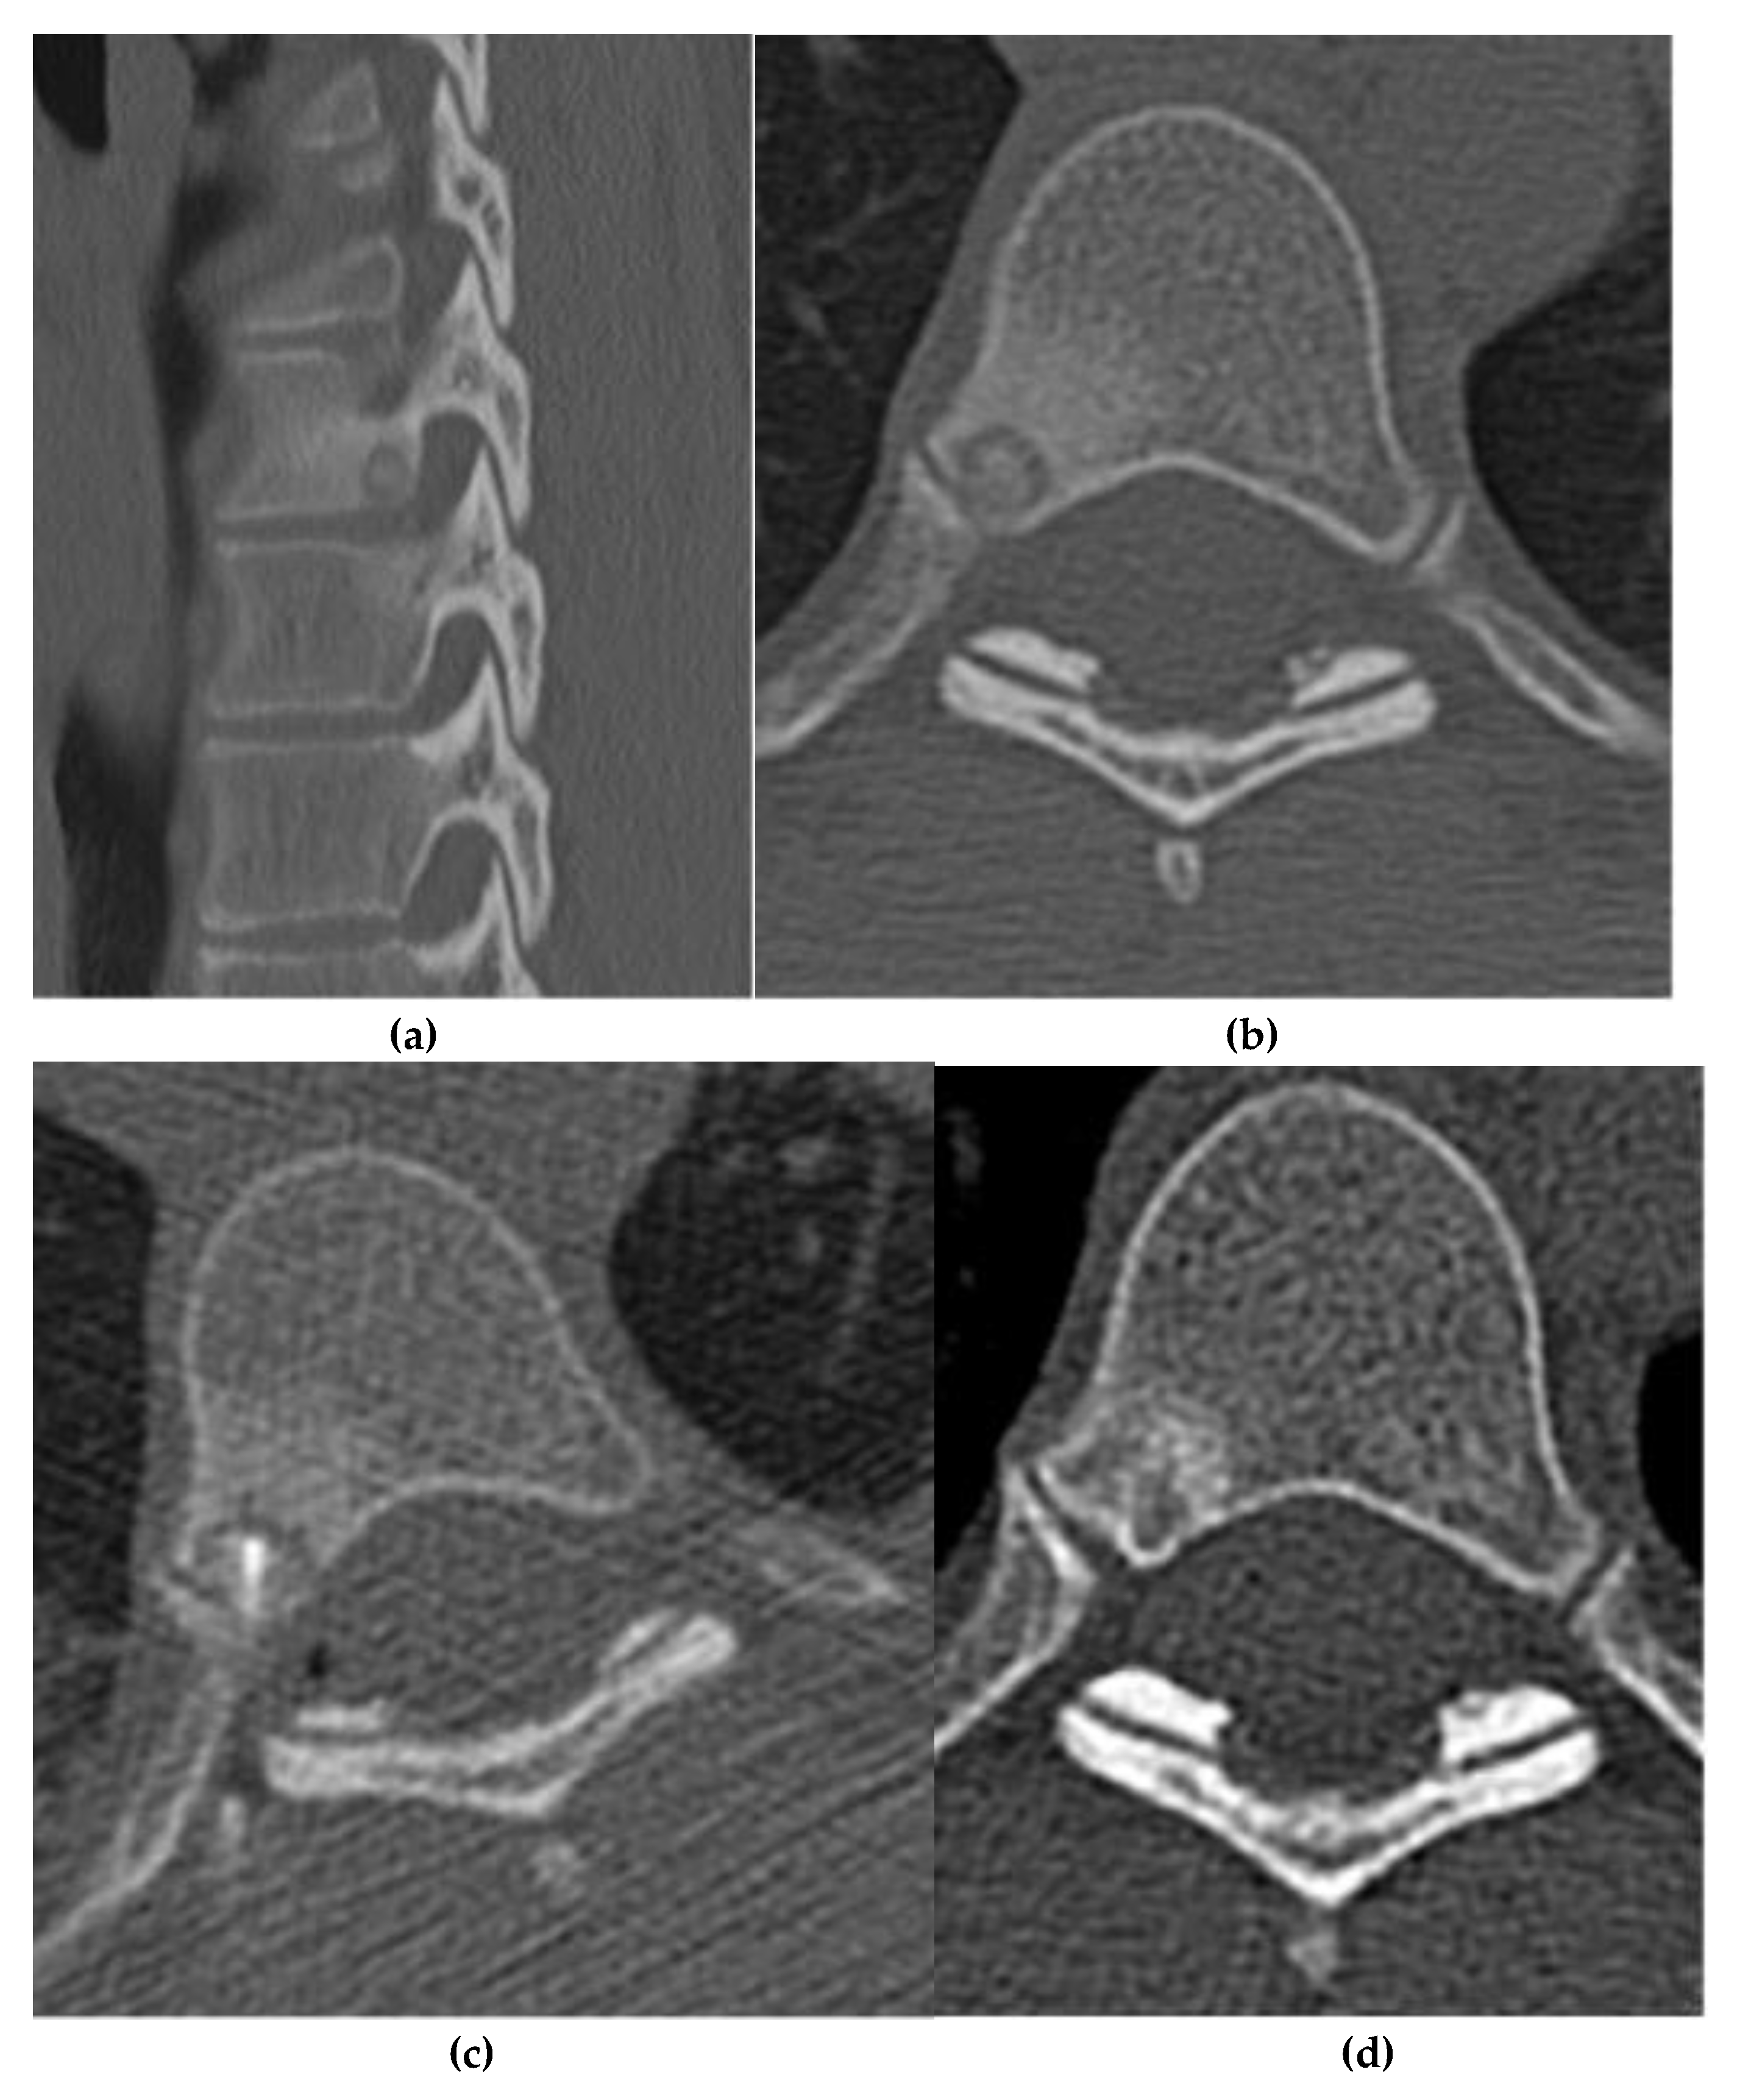

Osteoblastoma

Osteosarcoma